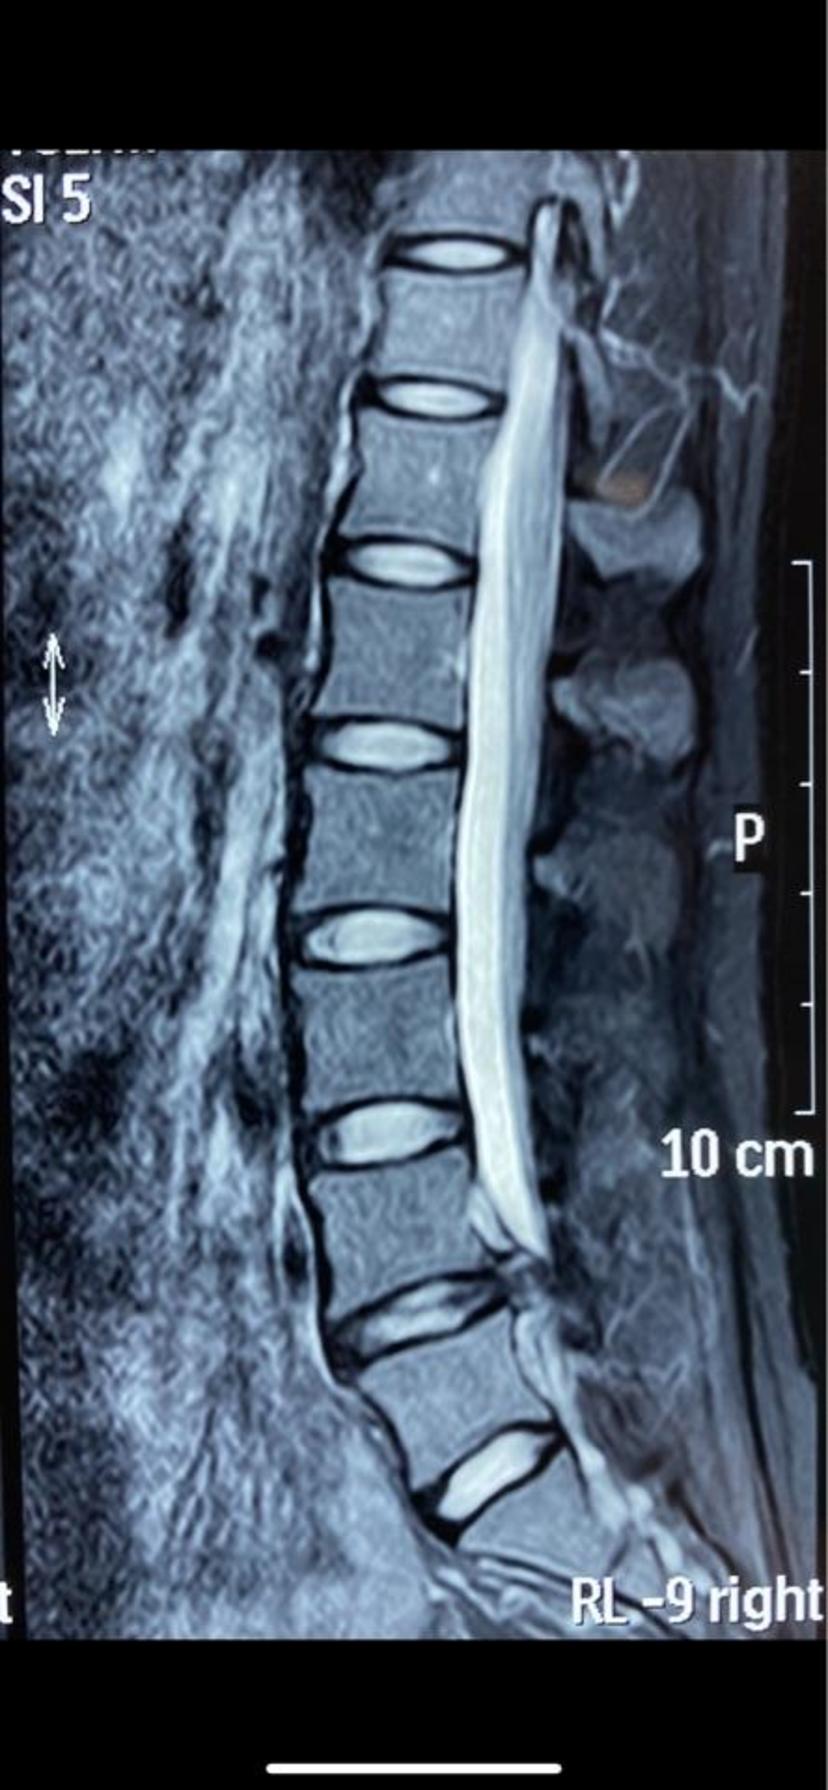

磁共振平扫显示左侧的神经根被挤压严重